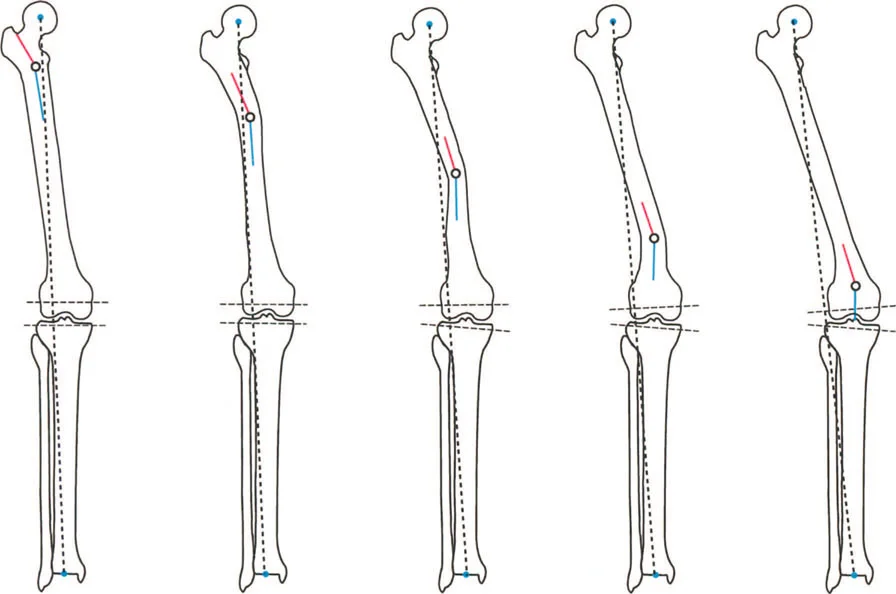

لطالما كان التركيز الأساسي في جراحة العظام، خاصة لطلبة الجراحة، ينصب على التشوهات الثابتة للأطراف السفلية. هذه التشوهات تشمل انحرافات العظام الثابتة، والتئام العظام بشكل خاطئ، وعدم التئامها، وتيبس المفاصل، وهي حالات يسهل قياسها وتحديدها عبر الأشعة السينية الثابتة. ولكن، لكي يتقن الجراح حقًا إعادة بناء الأطراف السفلية، وتخطيط عمليات قطع العظم (Osteotomy)، وجراحات استبدال المفاصل المعقدة، يجب عليه أن يتجاوز هذا الفهم التقليدي ويتعمق في العالم الحركي والسائل للتشوهات الديناميكية.

التشوهات الديناميكية هي اختلالات وظيفية تتأثر بموقع المفصل في الفراغ، ووظيفة العضلات، والأهم من ذلك، الطول الفعلي والتوجيه المكاني لأذرع الرافعة الهيكلية أثناء الحركة. على عكس التشوهات الثابتة التي تكون موجودة بغض النظر عن الحركة، فإن التشوهات الديناميكية تظهر بوضوح أو تتفاقم عندما يحاول المريض أداء حركة معينة، مثل المشي أو الوقوف.

أمثلة أخرى رئيسية للتشوهات الديناميكية تشمل "الورم الفخذي المفرط" (Severe Femoral Anteversion) و "الورك الأفحج" (Coxa Vara). في كلتا هاتين الشذوذات المعمارية، يتم تقصير الطول الفيزيائي لذراع الرافعة لعضلات المبعدة (Abductor muscles) بشكل مرضي بسبب التشوه العظمي نفسه. قد تكون عضلة الألوية الوسطى (Gluteus Medius) صحية تمامًا، ومعصبة جيدًا، وقادرة على توليد قوة بيولوجية طبيعية، لكنها تعاني من خلل وظيفي سريري عميق لأن ميزتها الميكانيكية قد سُلبت بسبب الهندسة الهيكلية المتغيرة. هذه الفئة الفرعية المحددة من الأمراض تُعرف باسم "تشوه في طول ذراع الرافعة".

في حين أن التشوهات الديناميكية تُناقش غالبًا في سياق أمراض الأعصاب والعضلات لدى الأطفال، فإن المبادئ البيوميكانيكية التي تحكمها تنطبق عالميًا على إعادة بناء العظام لدى البالغين. يشمل ذلك سيناريوهات إعادة البناء المعقدة للغاية، مثل استبدال مفصل الركبة الكلي (TKR) واستبدال مفصل الورك الكلي (THR) المرتبطة بالانحرافات الشديدة خارج المفصل. إن فهم الأذرع الرافعة هو المتطلب الأساسي لإتقان هذه التقنيات المتقدمة في جراحة المفاصل وقطع العظم، وهو ما يتقنه الأستاذ الدكتور محمد هطيف في ممارسته اليومية.

صاغ مصطلح "خلل وظيفة الذراع الرافعة" (Lever Arm Dysfunction) لأول مرة من قبل غيج (Gage) في عام 1991 لوصف التشوهات العظمية المعقدة التي تنشأ لدى الأطفال المتنقلين المصابين بالشلل الدماغي. ومع ذلك، يمتد تطبيقه إلى ما هو أبعد من جراحة الأعصاب والعظام لدى الأطفال ليشمل الممارسة اليومية لجراحي الإصابات وإعادة بناء العظام لدى البالغين.

بشكل خاص، يصف خلل وظيفة الذراع الرافعة حالة سريرية تتشوه فيها أذرع الرافعة الداخلية و/أو الخارجية بسبب سوء محاذاة العظام، أو التشوهات الالتوائية، أو تيبسات المفاصل الموضعية.